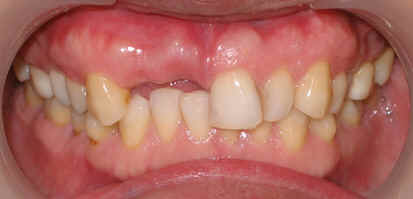

A 43 year-old lady has lost #7 and 8 due to caries for ~ 2 year. It appears that the ridge is wide (Fig.1). To place implants in ideal position, cone beam CT is planned. Models are mounted (Fig.2); diagnostic wax-up is finished (Fig.3). Drill sleeves (arrowheads in Fig.4; 10 mm long, 2.2 mm in diameter; Straumann) are placed lingual to the incisal (I) edges of the neighboring teeth. The position of drill sleeves is confirmed by CT: between the incisal edge and the cingulum (Fig.5). The cross sections at #7, 8 and 9 are shown in Fig. 6, 7 and 8, respectively. However, the long axis of the sleeve (S) or the natural tooth #9 is not aligned with that of the alveolar ridge. This orientation is good from prosthetic viewpoint, but we cannot place a long or wide implant. The lateral view of the three-dimensional image shows that the long axis of the crown (C) of #9 is not in line with that of its root/ridge (R, Fig.9). It appears that the trajectory of an implant should be not decided by wax-up, but should be adjusted to accommodate the morphology of the alveolar ridge. In all, the drill sleeve (S) should be moved and tilted more labially to place the longest and largest implant.